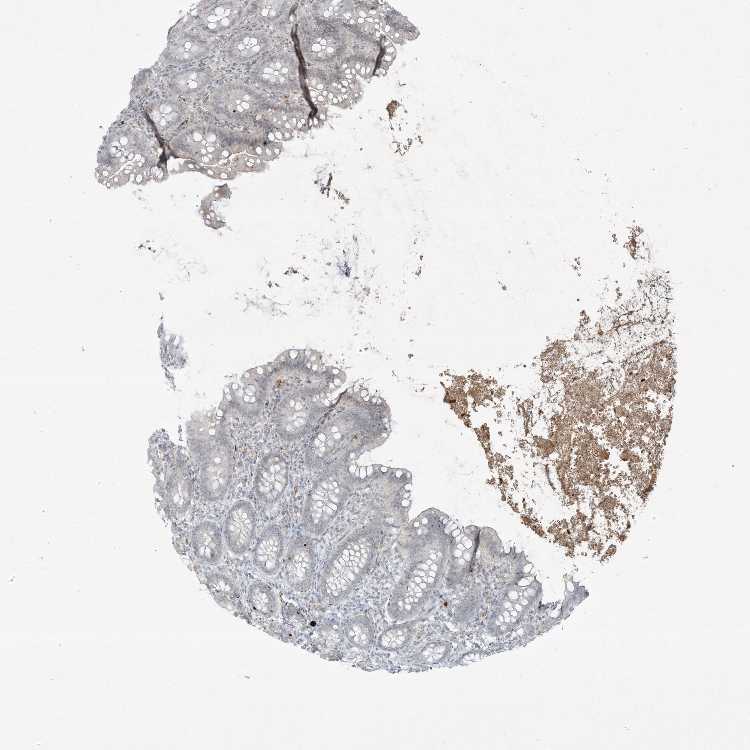

PAX6